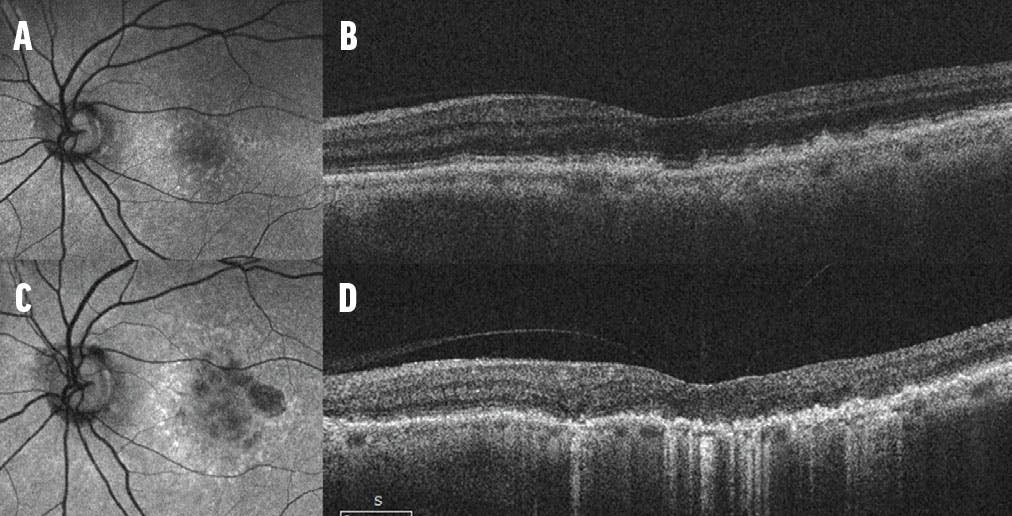

<p>Figure. This patient’s fundus autofluorescence documented intermediate dry AMD (A), and the OCT demonstrated multiple drusen (B). The patient progressed to patchy geographic atrophy with photoreceptor loss 8 years later (C), and OCT showed photoreceptor loss and increased transmission of the OCT beam (D). As this case demonstrates, progression from intermediate AMD to geographic atrophy may be faster than expected; thus, surgeons should be cautious when considering implanting an MFIOL in patients with intermediate AMD.</p>

Figure. This patient’s fundus autofluorescence documented intermediate dry AMD (A), and the OCT demonstrated multiple drusen (B). The patient progressed to patchy geographic atrophy with photoreceptor loss 8 years later (C), and OCT showed photoreceptor loss and increased transmission of the OCT beam (D). As this case demonstrates, progression from intermediate AMD to geographic atrophy may be faster than expected; thus, surgeons should be cautious when considering implanting an MFIOL in patients with intermediate AMD.